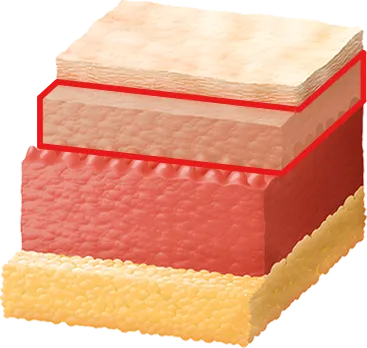

Cystic

Comedonal

Nodular

Papular

Pustular

Folliculitis

Scars

Pores